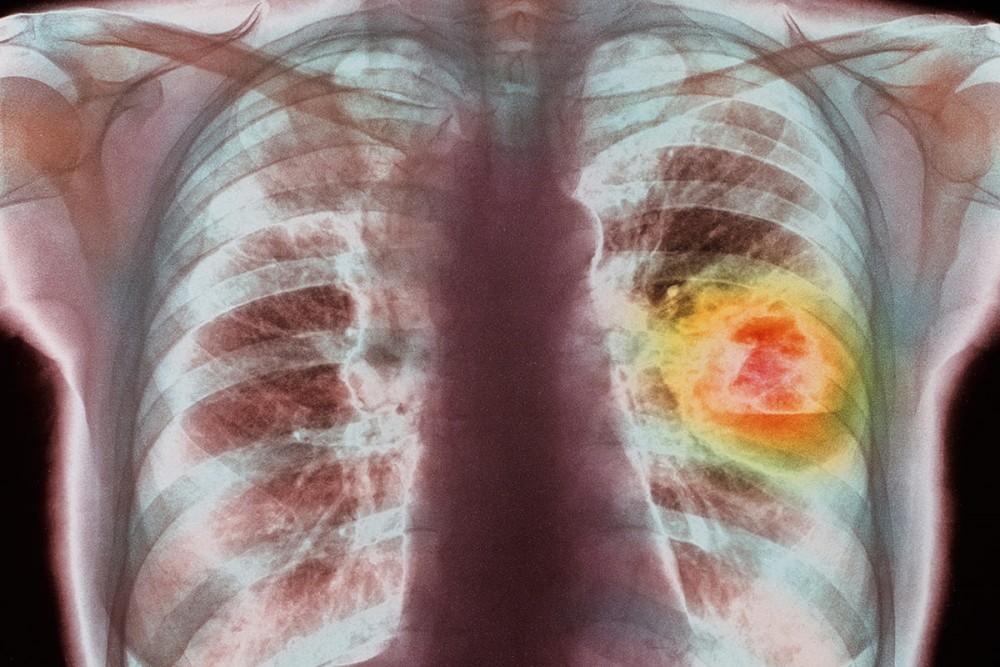

Рак легких — наиболее распространенное в мировой популяции злокачественное новообразование.

Ежегодно рак легкого в России диагностируют более чем у 50 тысяч пациентов, при этом рак легких занимает первое место (12%) в структуре заболеваемости населения злокачественными новообразованиями.

Мужчины болеют значительно чаще, чем женщины (в соотношении 9:1).